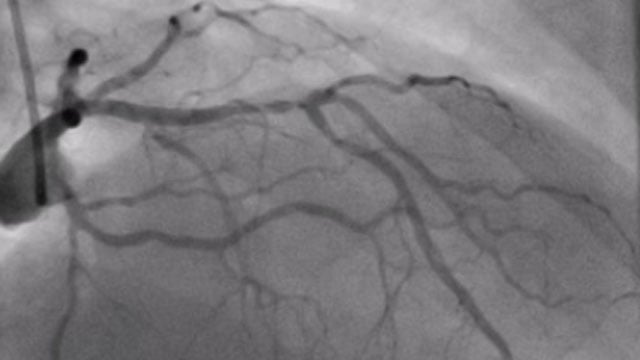

How to perform angiographic check after large-sheath removal in single access procedures

In the absence of other arterial access, this step-by-step tutorial shows how to perform anterograde angiography of the arterial axis after removal of the large sheath, making it easier to recognise and rapidly manage vascular complications such as arterial lesions and haemostasis failure.